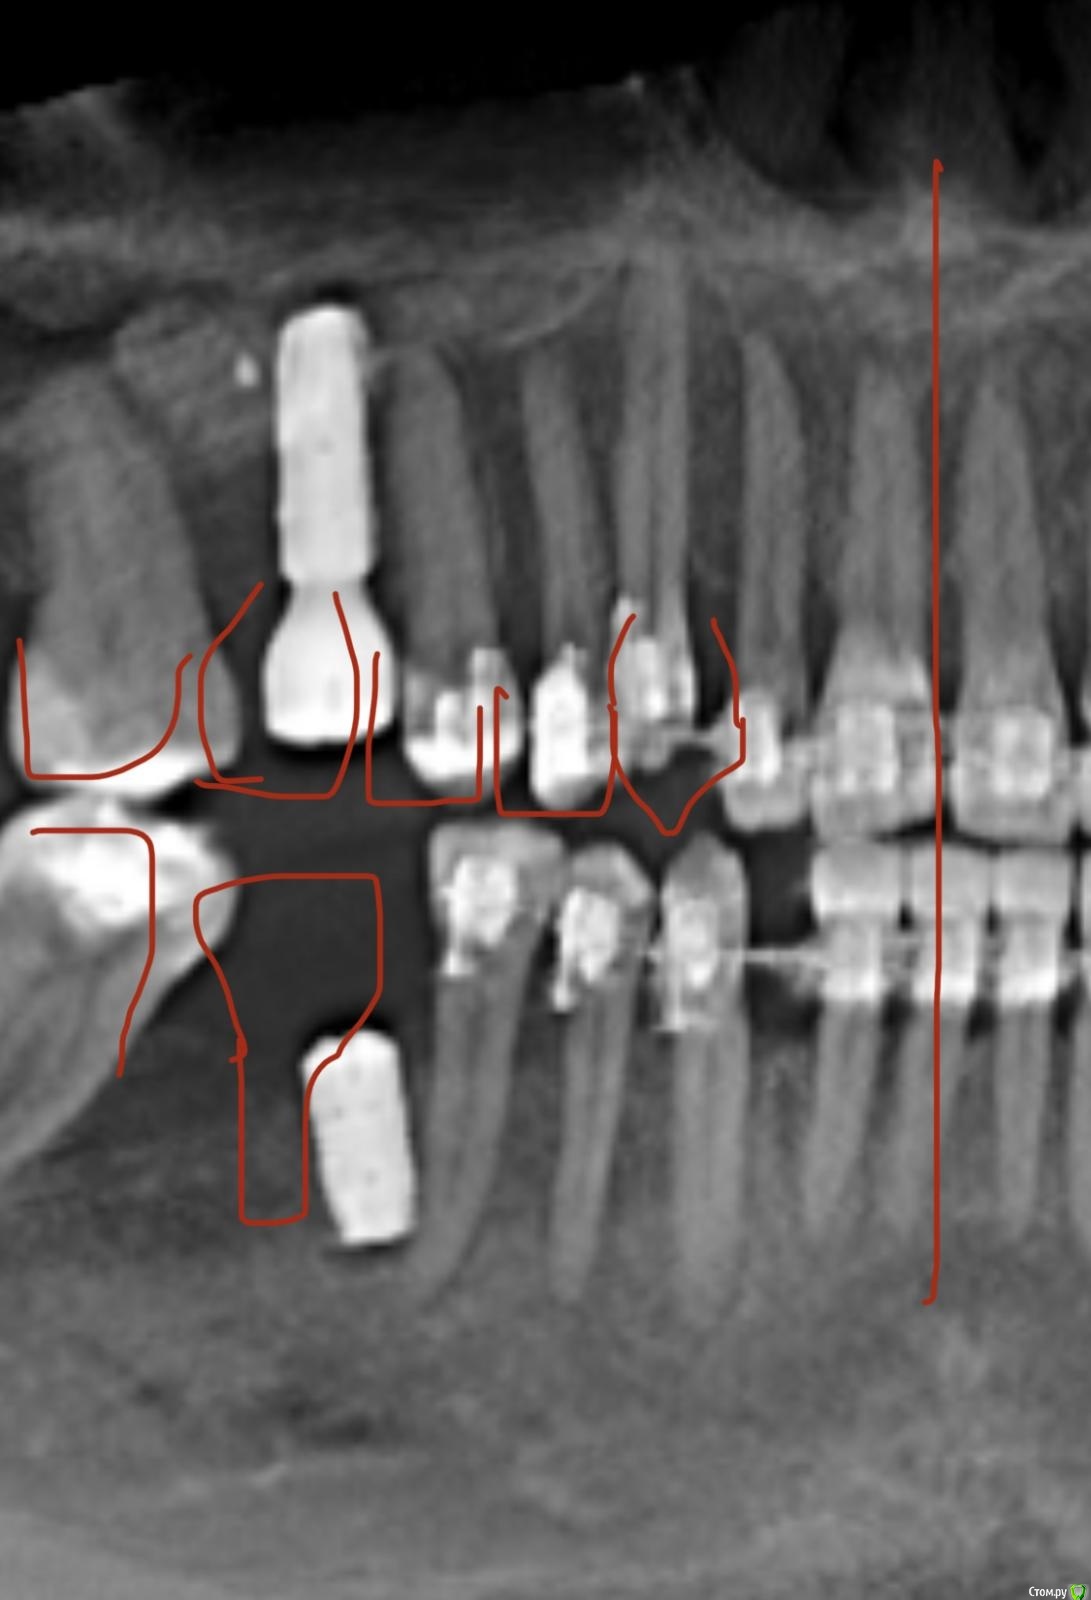

Тата Богачевская Опубликовано 24 октября, 2020 Поделиться Опубликовано 24 октября, 2020 Здравствуйте. Меньше месяца назад на место отсутствующего 46 зуба мне был установлен имплантат с расщеплением альвеолярного гребня. Операция прошла хорошо, никаких осложнений. В настоящий момент ничего не беспокоит. Тем не менее положение имплантата у меня вызывает беспокойство - слишком близко к корню 45 зуба и под углом к нему. Однако доктор уверяет, что положение имплантата нормальное, не идеальное конечно, но не критичное. Скажите, пожалуйста, угрожает ли такое положение имплантата 45 зубу, возможно ли будет в дальнейшем установить коронку в правильное положение? Или нужно удалить имплантат? Благодарю.https://yadi.sk/d/Tzd1aKb84eU3wQ Ссылка на комментарий

It'sGeorgy Опубликовано 24 октября, 2020 Поделиться Опубликовано 24 октября, 2020 Попробуйте перезалить КТ. Открывается не полностью, только панорамный вид.Если судить по панорамному виду, имплантат лучше переустановить. Ссылка на комментарий

red_butler Опубликовано 25 октября, 2020 Поделиться Опубликовано 25 октября, 2020 Имплант нужно переставить Ссылка на комментарий

колесников Опубликовано 25 октября, 2020 Поделиться Опубликовано 25 октября, 2020 4 месяцаИмплант 46 нужно убрать. Зуб 47ой дистализировать ортодонтически. Переустановить имплант 46 в правильной ортопедической позиции с десневой пластикой. К окончанию лечения вероятно будут вопросы к импланту 16,положение его платформы не самое оптимальное . 1 Ссылка на комментарий

колесников Опубликовано 25 октября, 2020 Поделиться Опубликовано 25 октября, 2020 (изменено) Поясните пожалуйста понятным для пациента языком, что значит "положение платформы 16 имплантата не самое оптимальное" .Я только на панорамный снимок ориентируюсь,возможно все не так как кажется. Мне представляется так:чтобы поставить клык (13) в зубной ряд,надо дистализировать 15,14 ,что создаст проблем для протезирования 16,который уже сейчас близко к 15 ,для моделирования коронки моляра 16. Вначале ортодонтия,после имплантация. Немного поторопились с имплантами. Или придётся удалить 15,чтобы не трогать имплант 16 Изменено 25 октября, 2020 пользователем колесников Ссылка на комментарий